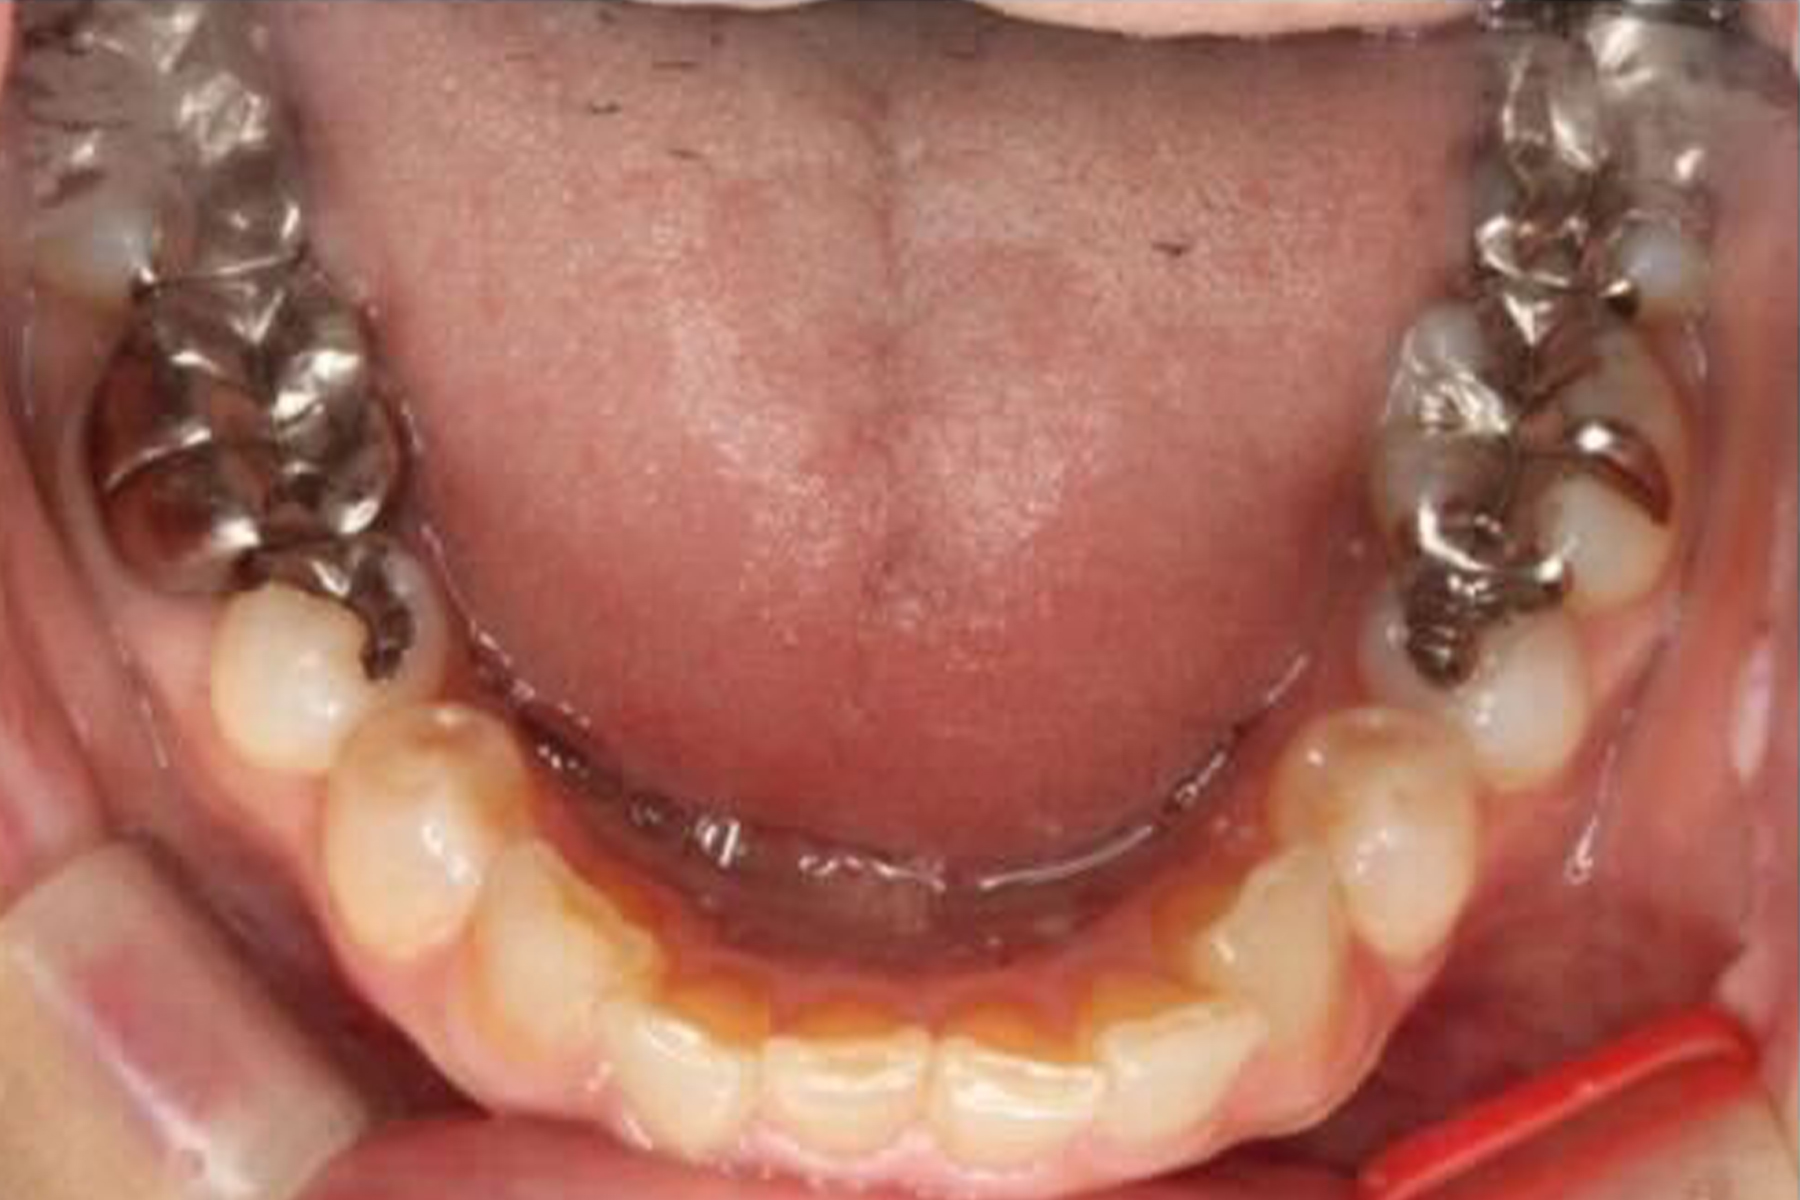

BEFORE

| 主訴 | 銀歯を白い歯に変えたい |